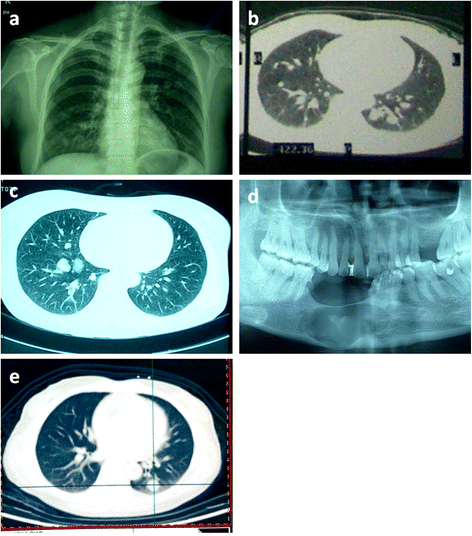

Malignant Ameloblastoma (metastatic Ameloblastoma) In The Lung: 3 Cases

diagnosticpathology.biomedcentral.com ameloblastoma malignant metastatic tumor misdiagnosis

Biopsy Proven Mucinous Adenocarcinoma In A 50-year-old Male

www.researchgate.net adenocarcinoma mucinous biopsy tnm bilateral manifesting

Biopsy liquid cancer lung biomarkers applications future gene application current cell diagnostics role separation techniques various isolation. Adenocarcinoma mucinous biopsy tnm bilateral manifesting. Ameloblastoma malignant metastatic tumor misdiagnosis